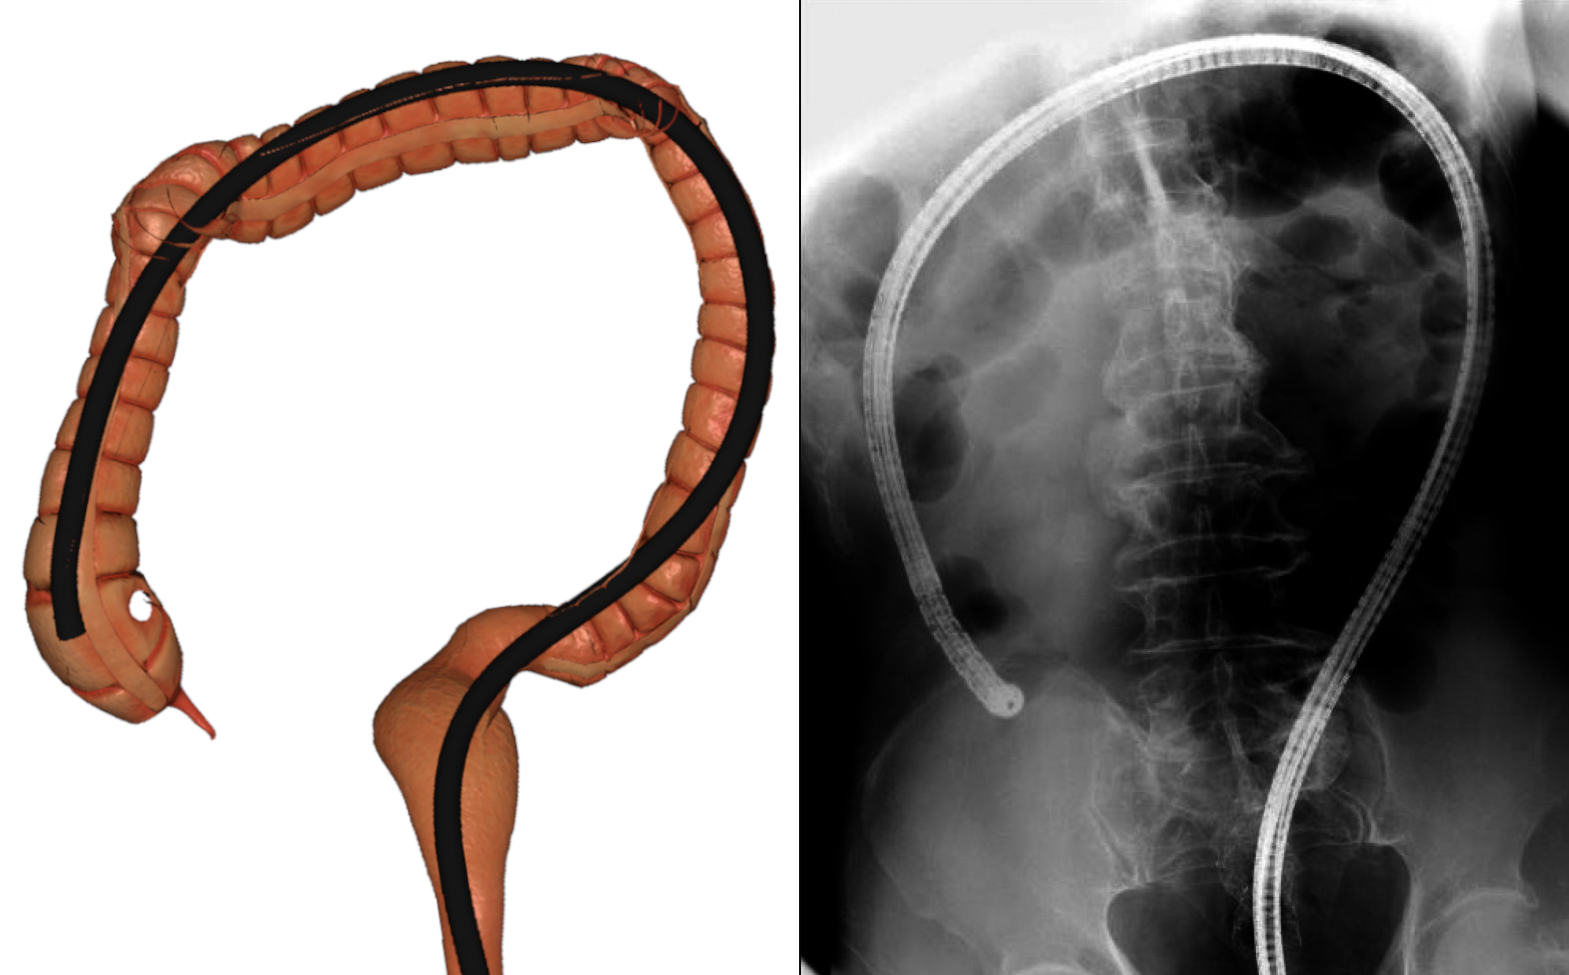

One of our main contributions is a simulation pipeline divided into three main parts, starting with the acquisition and reconstruction of the colon from a real patient CT (a). Then, the colon centerline is extracted and used to build a spline skeleton (b), which will be used to model the colon and the endoscope. The physical deformation is produced using an XPBD formulation and a tailored collision detection method during the simulation (c).